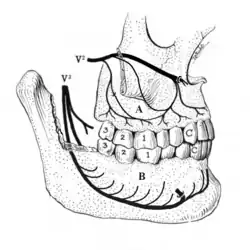

1: crown, 2: root, 3: enamel, 4: dentin and dentin tubules, 5: pulp chamber, 6: blood vessels and nerve within root canal, 7: periodontal ligament, 8: apex and periapical region, 9: alveolar bone.

V2: maxillary division of trigeminal nerve, V3: mandibular division of trigeminal nerve, A: the superior alveolar nerves and plexus, B: the inferior alveolar nerve and plexus running in the body of the mandible.

A tooth is composed of an outer shell of calcified hard tissues (from hardest to softest: enamel, dentin, and cementum), and an inner soft tissue core (the pulp system), which contains nerves and blood vessels. The visible parts of the teeth in the mouth – the crowns (covered by enamel) – are anchored into the bone by the roots (covered by cementum). Underneath the cementum and enamel layers, dentin forms the bulk of the tooth and surrounds the pulp system. The part of the pulp inside the crown is the pulp chamber, and the central soft tissue nutrient canals within each root are root canals, exiting through one or more holes at the root end (apical foramen/foramina). The periodontal ligament connects the roots to the bony socket. The gingiva covers the alveolar processes, the tooth-bearing arches of the jaws.[42]: 1–5

Enamel is not a vital tissue, as it lacks blood vessels, nerves, and living cells.[18] Consequently, pathologic processes involving only enamel, such as shallow cavities or cracks, tend to be painless.[18] Dentin contains many microscopic tubes containing fluid and the processes of odontoblast cells, which communicate with the pulp. Mechanical, osmotic, or other stimuli cause movement of this fluid, triggering nerves in the pulp (the "hydrodynamic theory" of pulp sensitivity).[19] Due to the close relationship between dentin and pulp, they are frequently considered together as the dentin-pulp complex.[43]: 118

The pain pathway is mostly transmitted via myelinated (sharp or stabbing pain) and unmyelinated C nerve fibers (slow, dull, aching, or burning pain) of the trigeminal nerve, which supplies sensation to the teeth and gums via many divisions and branches.[18] Initially, pain is felt while noxious stimuli are applied (such as cold). Continued exposure decreases firing thresholds of the nerves, allowing normally non-painful stimuli to trigger pain (allodynia). Should the insult continue, noxious stimuli produce larger discharges in the nerve, perceived as more intense pain. Spontaneous pain may occur if the firing threshold is decreased so it can fire without stimulus (hyperalgesia). The physical component of pain is processed in the medullary spinal cord and perceived in the frontal cortex. Because pain perception involves overlapping sensory systems and an emotional component, individual responses to identical stimuli are variable.[10]: 474–475